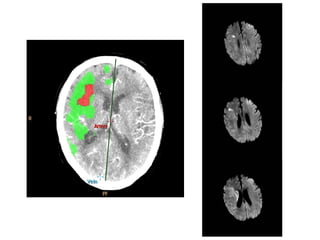

Multimodal Imaging

Multimodal CT

• Typically includes non-

contrast CT, perfusion CT,

and CTA

• Two types of perfusion CT

– Whole brain perfusion CT

– Dynamic perfusion CT

Multimodal MRI

• Standard MRI sequences

(T1 weighted, T2 weighted,

and proton density) are

relatively insensitive to

changes in cerebral

ischemia

• Multimodal adds diffuse-

weighted imaging (DWI)

and PWI (perfusion-

weighted imaging)

Multimodal Imaging Multimodal CT •Typically includes non- contrast CT, perfusion CT, and CTA • Two types of perfusion CT – Whole brain perfusion CT – Dynamic perfusion CT Multimodal MRI • Standard MRI sequences (T1 weighted, T2 weighted, and proton density) are relatively insensitive to changes in cerebral ischemia • Multimodal adds diffuse- weighted imaging (DWI) and PWI (perfusion- weighted imaging)